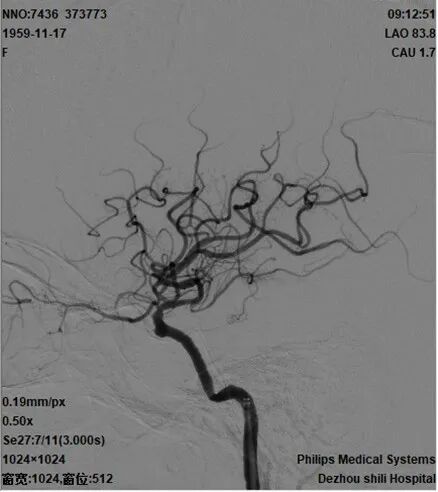

2021-12-3 DSA

重要影像结论:2021-6-25右侧基底节区新发脑梗死,2021-12-3提示右侧颈内动脉海绵窦段重度狭窄。